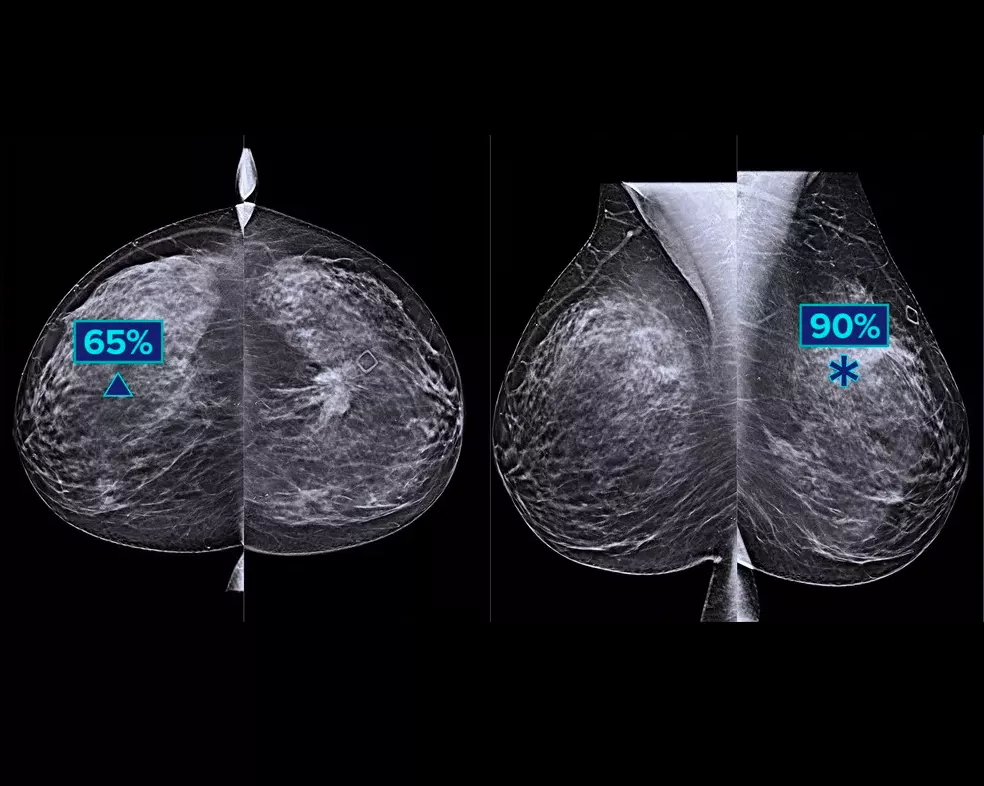

Un algorithme d’intelligence artificielle conçu pour aider les radiologues à effectuer des diagnostics et à détecter un cancer du sein1-3 à partir d’images de tomosynthèse obtenues à l’aide du système Hologic Dimensions Mammography®. L’algorithme localise les lésions susceptibles de représenter un cancer du sein en étudiant chaque coupe de l’ensemble des images de tomosynthèse. Les zones suspectes sont mises en évidence sur le poste de travail du radiologue pour permettre une lecture simultanée et aider à l’interprétation.

L’algorithme recherche les 3 principaux groupes de lésions suspectes : calcifications, masses, densités et distorsions ; ainsi que les combinaisons de ces lésions. Les données de sortie peuvent varier selon les postes de travail.

Usage préconisé : Genius AI Detection est un logiciel de détection et de diagnostic assisté par onlinateur (CADe/CADx) destiné à être utilisé avec des systèmes de tomosynthèse mammaire numérique (DBT) compatibles pour identifier et marquer des régions d'intérêt y compris les densités de tissus mous (masses, distorsions architecturales et asymétries) et les calcifications, lors de la lecture des examens de DBT à partir de systèmes de DBT compatibles, et pour fournir des scores de confiance qui permettent d'évaluer la certitude des résultats et un score du cas. Le dispositif vise à faciliter l'interprétation des examens de tomosynthèse mammaire numérique de manière simultanée lorsque le médecin interprète confirme ou infirme les résultats lors de la lecture de l'examen.